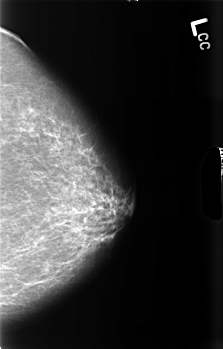

B_3458_1.LEFT_CC

LEFT_CC LINES 4528 PIXELS_PER_LINE 2888 BITS_PER_PIXEL 12 RESOLUTION 50 NON_OVERLAY